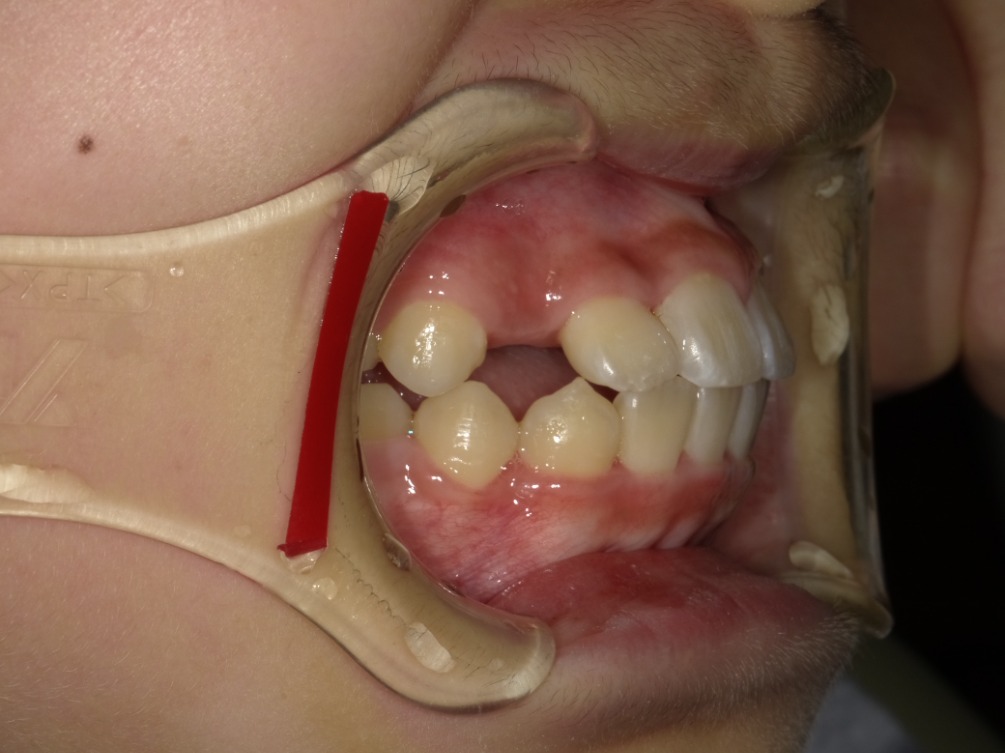

AFTER

症例集 インビザライン 正面

症例集 インビザライン 右横

スペース不足を整えるために、歯の表面にアタッチメント(白い突起)をつけ、IPR(歯と歯の間を削る)を行いました。

スペース不足を放置していた場合、叢生と言って歯が重なって生えてくる可能性の高い状態でした。

そのため、治療開始時には右下の前から3番目の永久歯の生えるスペースがありませんでした。

矯正治療を行うことで、スペースができ、治療後には正しい位置に生えています。